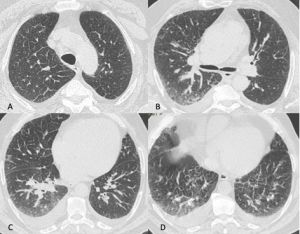

Figura 1: Uomo di 75 anni con infezione da SARS-CoV-2. Le immagini TC assiali (A-B-C-D) e ricostruzioni MPR sul piano sagittale (E) e coronale (F) mostrano la tipica presentazione della polmonite da COVID-19 caratterizzata dalla presenza di aree di aumentata densità con aspetto a “vetro smerigliato” cui si associa ispessimento liscio dei setti interlobulari che mostrano prevalente distribuzione subpleurica. La localizzazione delle aree di iperdensità in sede subpleurica è caratteristica di questa infezione come evidenziato particolarmente nell’immagine A in cui le aree a “vetro smerigliato” si dispongono lungo la scissura del lobo accessorio dell’azygos e nell’immagine E in cui è evidente la distribuzione delle alterazioni lungo le scissure.

Figura 2: Uomo di 41 anni con infezione da virus dell’Influenza A, giunge al Pronto Soccorso con febbre, tosse, malessere e lieve dispnea. La TCAR eseguita all’ingresso mostra nelle scansioni assiali (A-B) e nella ricostruzione MPR coronale (C) la presenza di sfumati micronoduli centrolobulari nel lobo superiore destro e nel lobo medio e di aree di aumentata densità con aspetto in parte a "vetro smerigliato" ed in parte consolidativo nel lobo inferiore destro.

Figura 3: Uomo di 65 immunocompromesso affetto da polmonite da Citomegalovirus. Le immagini TCAR assiali (A-B-C) e la ricostruzione MPR coronale (D) mostrano il tipico pattern caratterizzato dalle presenza di "vetro smerigliato" diffuso in entrambi i polmoni con distribuzione simmetrica, si associa la presenza di alcune aree di aumentata densità con aspetto consolidativo in entrambi i lobi inferiori.

Figura 4: Donna di 78 anni con diagnosi di Linfoma di Hodgkin. Le immagini assiali (A-B-C) mostrano il parenchima polmonare normale. Un anno dopo la paziente giunge al Pronto Soccorso per un rapido peggioramento della funzionalità respiratoria, dispnea e tosse. La TCAR eseguita alcuni giorni dopo il ricovero nel reparto di Malattie Infettive (D-E-F) mostra la presenza in entrambi i polmoni di "vetro smerigliato" diffuso con relativo risparmio delle zone sub-pleuriche e la comparsa di formazioni pseudocistiche nel lobo superiore sinistro (frecce in D ed E). L’ipotesi formulata e poi confermata dal laboratorio è stata quella di polmonite da Pneumocystis Jirovecii.